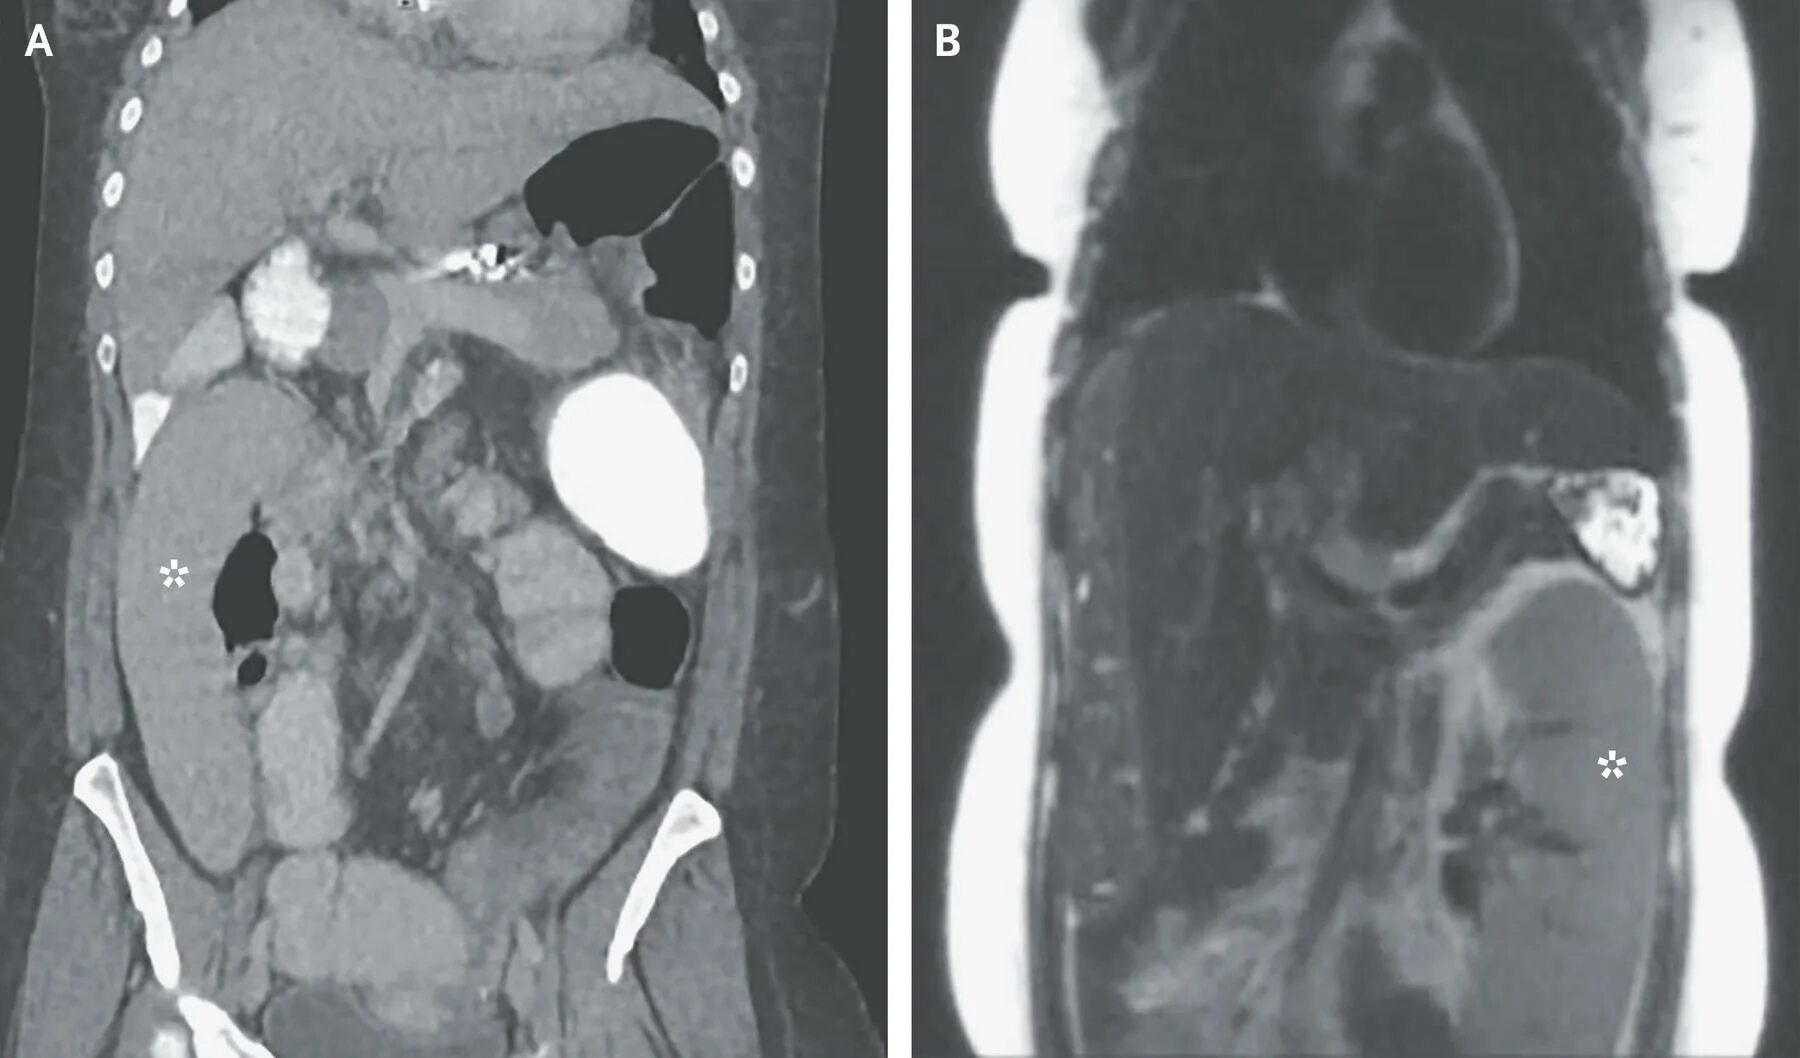

Уменьшение селезенки